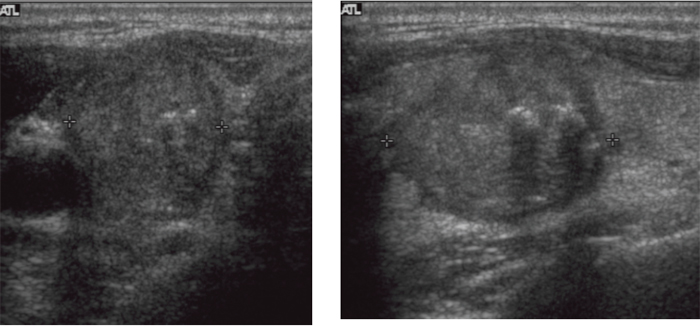

Figure 2: A 52-year-old woman with a papillary thyroid carcinoma with BRAF mutation in right thyroid lobe. Transverse (A) and longitudinal (B) ultrasonographic images show a 2.2-cm solid mass with spiculated margin, irregular shape, hypoechogenicity, non-parallel orientation, and micro- and macrocalcifications. This mass was classified as K-TIRADS category 5. After surgery, central lymph nodes were confirmed as metastases and TNM stage was classified as III. There was no recurrence during 11.4 years of follow-up.

Figure 3: A 56-year-old woman with a papillary thyroid carcinoma with TERT+BRAF mutations in left thyroid lobe. Transverse (A) ultrasonographic image shows a 3.0-cm solid mass with spiculated margin, irregular shape, hypoechogenicity, non-parallel orientation, and microcalcifications. Transverse (B) ultrasonographic image shows an enlarged lymph node with increased cortical echogenicity and cystic changes in left level IV. The main mass was classified as K-TIRADS category 5 and the level IV lymph node was considered metastatic. After surgery, level IV lymph nodes were confirmed as metastases and TNM stage was classified as IV. Bilateral lung metastases and operative bed recurrences were diagnosed 4.4 years after surgery.